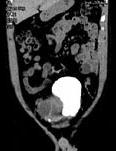

问题 男,34岁,右下腹持续性隐痛半月,排尿时加重入院,CT检查如图所示,下列说法错误的是 ( )

选项 A、该囊性病变考虑来源于精囊 B、此囊性病变为右精囊腺囊肿 C、膀胱右后下方囊性病变 D、膀胱向下,向后移位 E、右肾缺如

答案 D